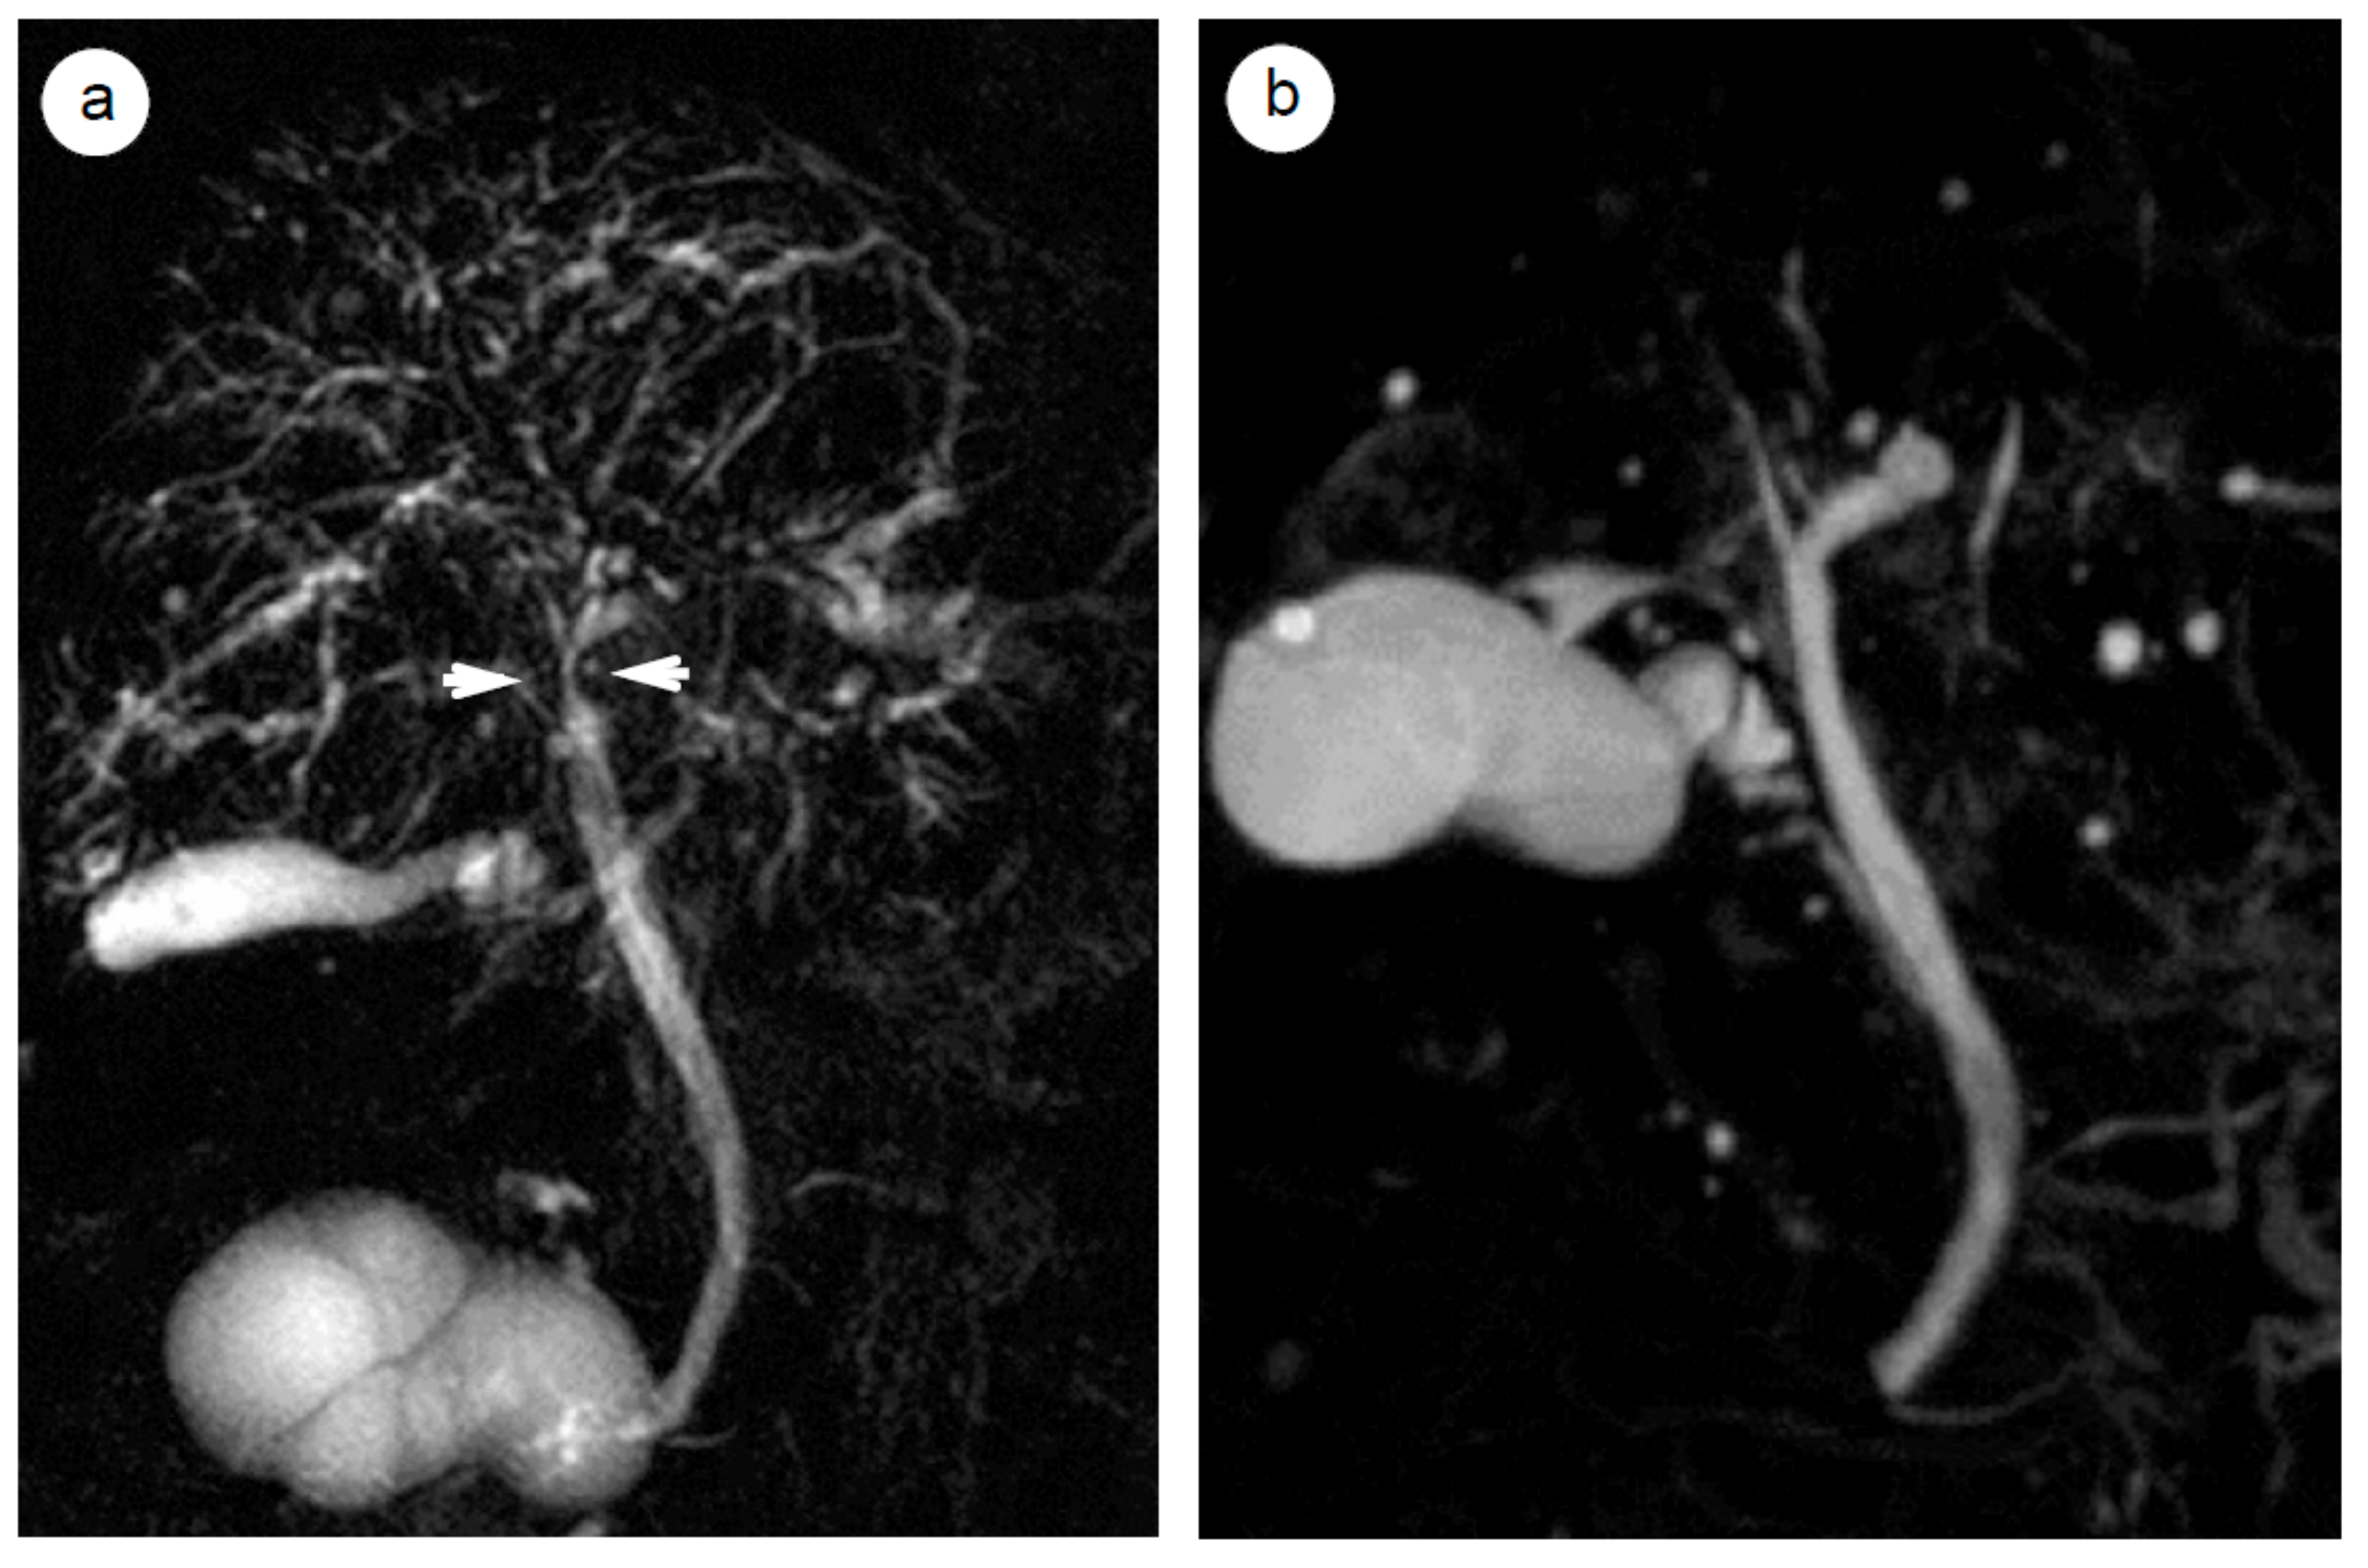

- Ishikawa, T.; Itoh, A.; Kawashima, H.; Ohno, E.; Itoh, Y.; Nakamura, Y.; Hiramatsu, T.; Miyahara, R.; Ohmiya, N.; Haruta, J.; et al. Peripancreatic vascular involvements of autoimmune pancreatitis. J. Gastroenterol. Hepatol. 2012, 27, 1790–1795. [Google Scholar] [CrossRef]

- Hara, N.; Kawaguchi, M.; Takeda, K.; Zen, Y. Retroperitoneal disorders associated with IgG4-related autoimmune pancreatitis. World J. Gastroenterol. 2014, 20, 16550–16558. [Google Scholar] [CrossRef]